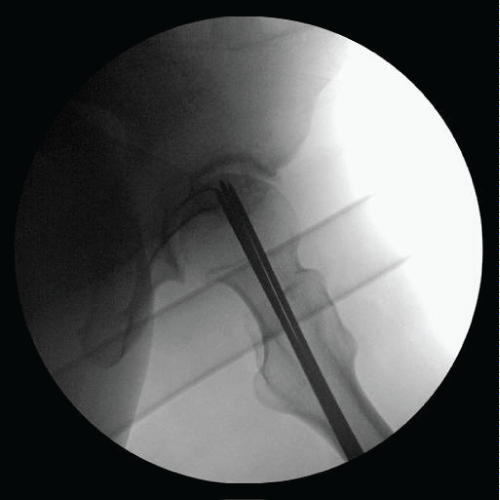

MG is a 31 yo F who presented with left hip pain for over a decade. MRI and radiographs had been obtained prior to presentation to our office which showed anterior quadrant cystic changes in the femoral head consistent with AVN in the pre-collapse state. On physical exam, the patient had excellent range of motion. The patient had already tried and failed conservative measures such as oral pain control, CSI, and protected weight bearing. She elected to undergo core decompression of the affected femoral head. At one year postoperatively she has limited improvement in her pain and continues to rehabilitate Figure 1, Figure 2, Figure 3, Figure 4 and Figure 5.

Figure 4: Intraoperative radiograph. View Figure 4

Figure 5: Intraoperative radiograph. View Figure 5

While the Ficat Staging system is the primary classification tool used in research settings, we generally determine treatment based on whether the lesion is pre-collapse or post-collapse. Our algorithm is shown in brief in Figure 1. Once a patient has progressed to post-collapse stage (we include patients with subchondral collapse (crescent sign) as post-collapse lesions), there are few if any treatments short of THA that can offer patients predictable outcomes. It is the patients who are pre-collapse and symptomatic in which we try our hardest to preserve the hip joint and delay arthroplasty. We have found that in young patients with a pre-collapse lesion, a small Kerboul angle (< 200), and a medially based lesion (closer to the fovea) have the best chance of achieving acceptable outcomes without arthroplasty. When the lateral pillar is maintained, as in medially-based focal lesions, the support of the femoral head remains adequate and there is a slower disease progression overall. In these select patients we offer core decompression in an attempt to preserve the native joint if possible. Our technique is to use a more proximal start site for core decompression, as Colwell, et al. showed that there is an increased risk of immediate postoperative fracture in cores that were taken distal to the vastus ridge [30]. We use a series of 3.2 mm Steinman pins percutaneously introduced into the femoral head to make 3 small diameter core decompression sites as originally described by Mont, et al. [31]. We augment Mont’s described procedure by over drilling the center most pin with a 4.5 mm drill and arthroscopic long-handle curette. Additionally, we have begun augmenting our core decompression with the use of concentrated iliac crest bone aspirate, which has recently been shown to significantly improve the clinical outcomes of this procedure [32]. Postoperatively, we instruct our patients to be toe touch weight-bearing for 6 weeks and 6 weeks of partial weight-bearing to allow for bone deposition and healing.